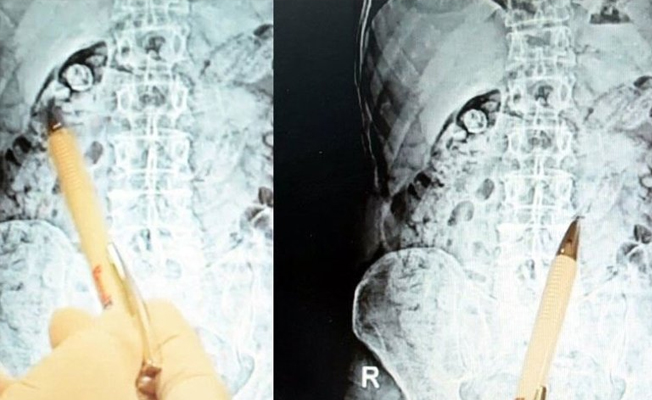

İzmir'in Torbalı ilçesinde polisin şüphe üzerine gözaltına aldığı İran uyruklu E.M. (34) ve P.S.'nin (55) mide ve bağırsaklarında 116 kapsül halinde toplam 810 gram metamfetamin ele geçirildi.

İl Emniyeti Narkotik Suçlarla Mücadele Şube Müdürlüğü ekipleri, Torbalı'da uyuşturucu satıcılarına yönelik çalışma kapsamında İran uyruklu E.M. ve P.S.'ye kimlik kontrolü yapmak istedi. Kontrolde herhangi bir suç unsuruna rastlanmazken, E.M. ve P.S.'nin davranışlarından şüphelenen polis, zanlıları gözaltına aldı. Uyuşturucu maddeyi kapsül halinde yutarak saklayabilecekleri ihtimali üzerine şüpheliler, hastaneye götürüldü. Hastanede çekilen röntgen filminde iki şüphelinin de mide ve bağırsaklarında 116 kapsül halinde toplam 810 gram metamfetamin bulundu. Yapılan cerrahi operasyonla uyuşturucu maddeler şüphelilerin vücutlarından çıkarıldı.